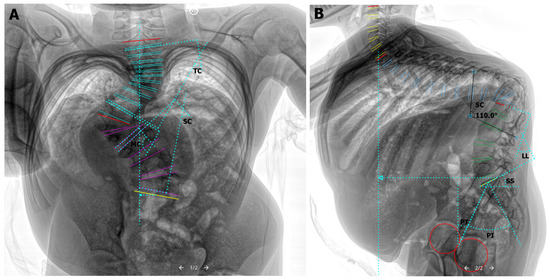

Figure 3.

Standing, pre-operative total spine AP & lateral X-ray images with sagittal and coronal alignment measurements. Curve type 5C + (L)–Lenke classification of AIS [17]. (A) (Anterior-posterior)–C7PL 1.54 cm; Major Cobb [MC] 69.9°, T12 Superior-L2 Inferior; Secondary Cobb [SC] 53.8°, L3 Superior-L5 Inferior; Tertiary Cobb [TC] 38.1°, T2 Superior-T11 Inferior. (B) (Lateral)–Sagittal Pelvic Tilt [PT] 25.3°; Pelvic Incidence [PI] 52.3°; Sacral Slope [SS] 27.1°; Lumbar Lordosis [LL] 45.4°; Sagittal Cobb [SC]-thoracolumbar kyphotic deformity of 110°, T9 Superior-L2 Inferior; Thoracic Kyphosis T4-T12 69.1°.